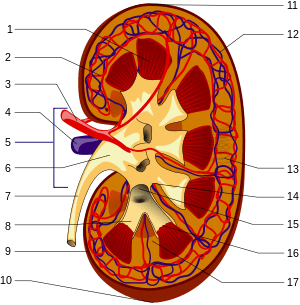

A human kidney (click on image for description). | |